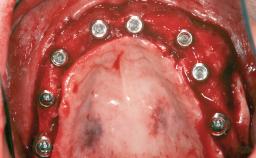

Shell Technique for Horizontal and Vertical Maxillary Bone Augmentation in a Partially Edentulous Patient with Aggressive Periodontal Disease

# of Implants 3

Type of Implants One-Piece

Attachment One-Piece

Bone Augmentation Horizontal|Staged|Vertical

Augmentation Materials Autogenous chips|Autogenous block(s)|Xenogenous